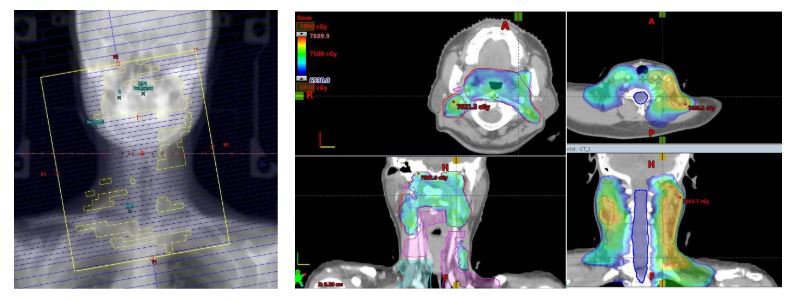

Bước 3: Lập kế hoạch xạ trị VMAT

Bệnh nhân đầu tiên ung thư vòm họng giai đoạn T3N2bM0